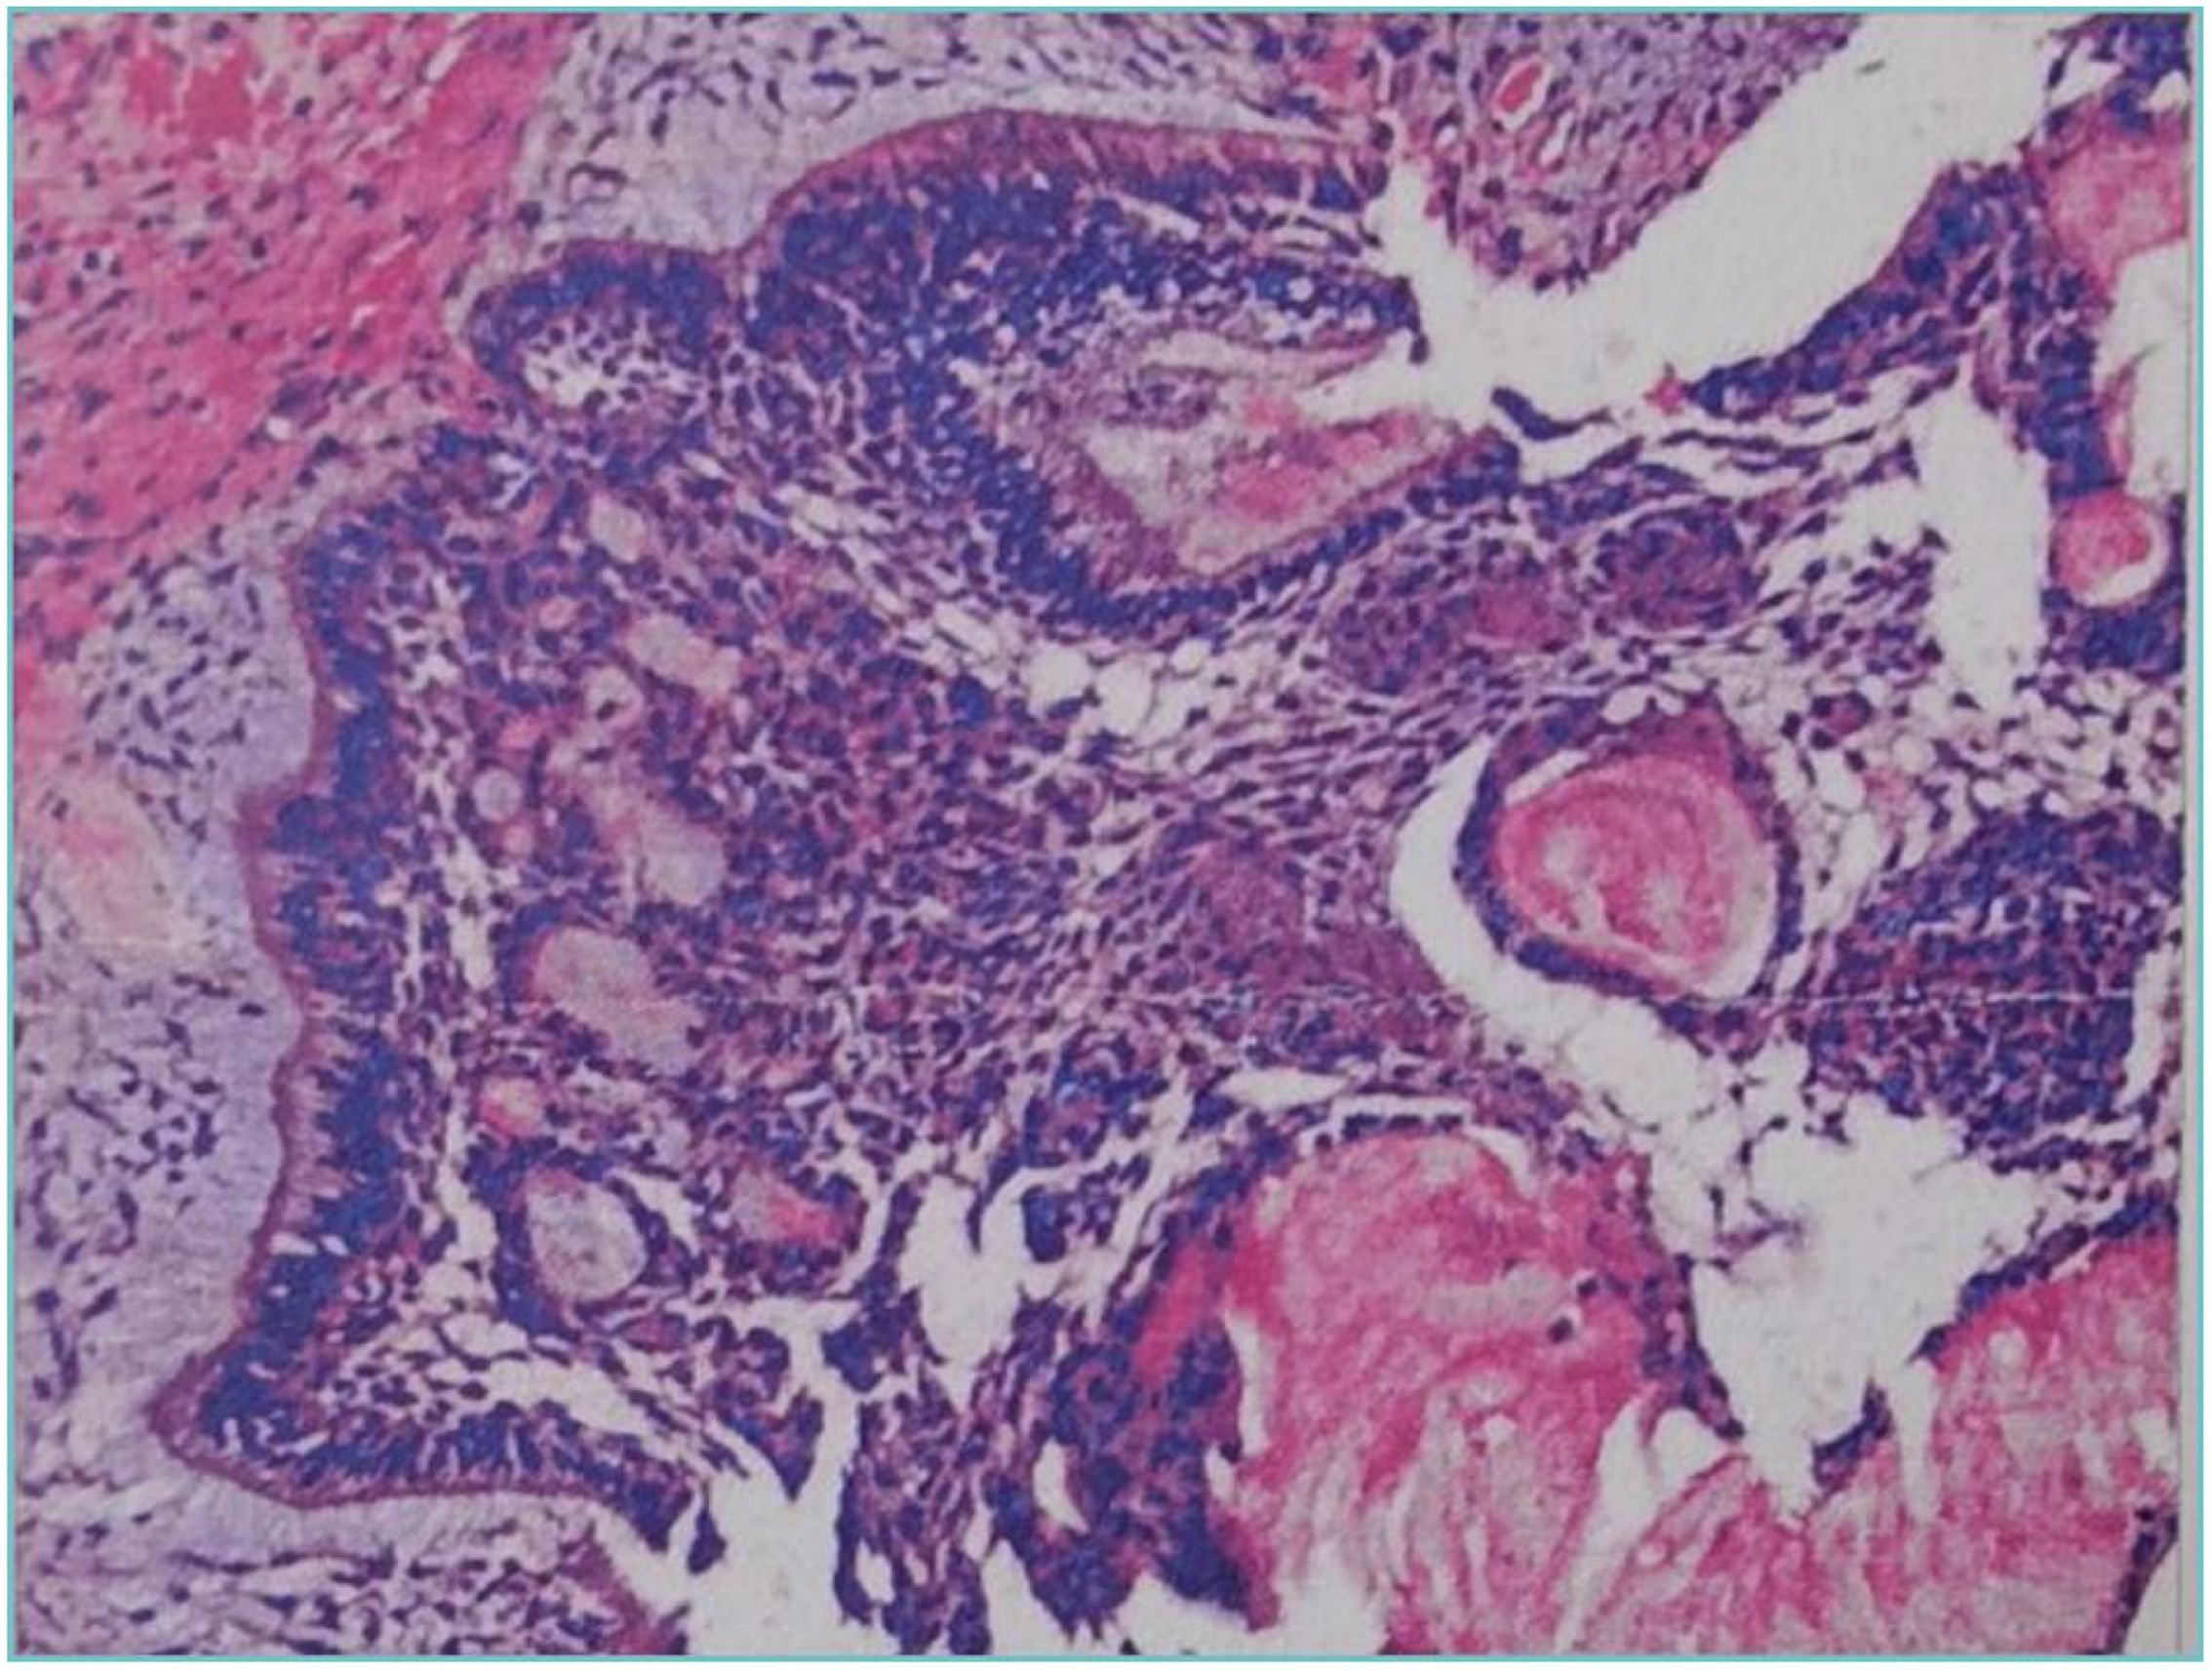

Dentinogenic ghost cell tumor (DGCT) is a rare odontogenic neoplasm that presents with nonspecific clinical manifestations and imaging features. It is more prevalent in elderly patients, with cases in children being extremely rare. This article presents a case study of a 10-year-old male patient who exhibited symptoms of swelling and pain in the left cheek for a duration of two weeks. Cone beam computed tomography (CBCT) demonstrated a hypodense lesion involving the left maxilla, with extension into the maxillary sinus and buccal cortical expansion. The patient underwent decompression, and histopathological examination of the intraoperative specimen suggested a diagnosis of calcifying odontogenic cyst (COC). One year after decompression, the patient underwent a tumor resection and the diagnosis of DGCT was confirmed by the post-operative pathology. Six months after tumor resection, CBCT showed complete bone remodelling in the lesion area. The patient is currently undergoing regular follow-up. This case provides an important reference for the diagnosis and treatment of pediatric DGCT, helping clinicians to develop individualised treatment plans.